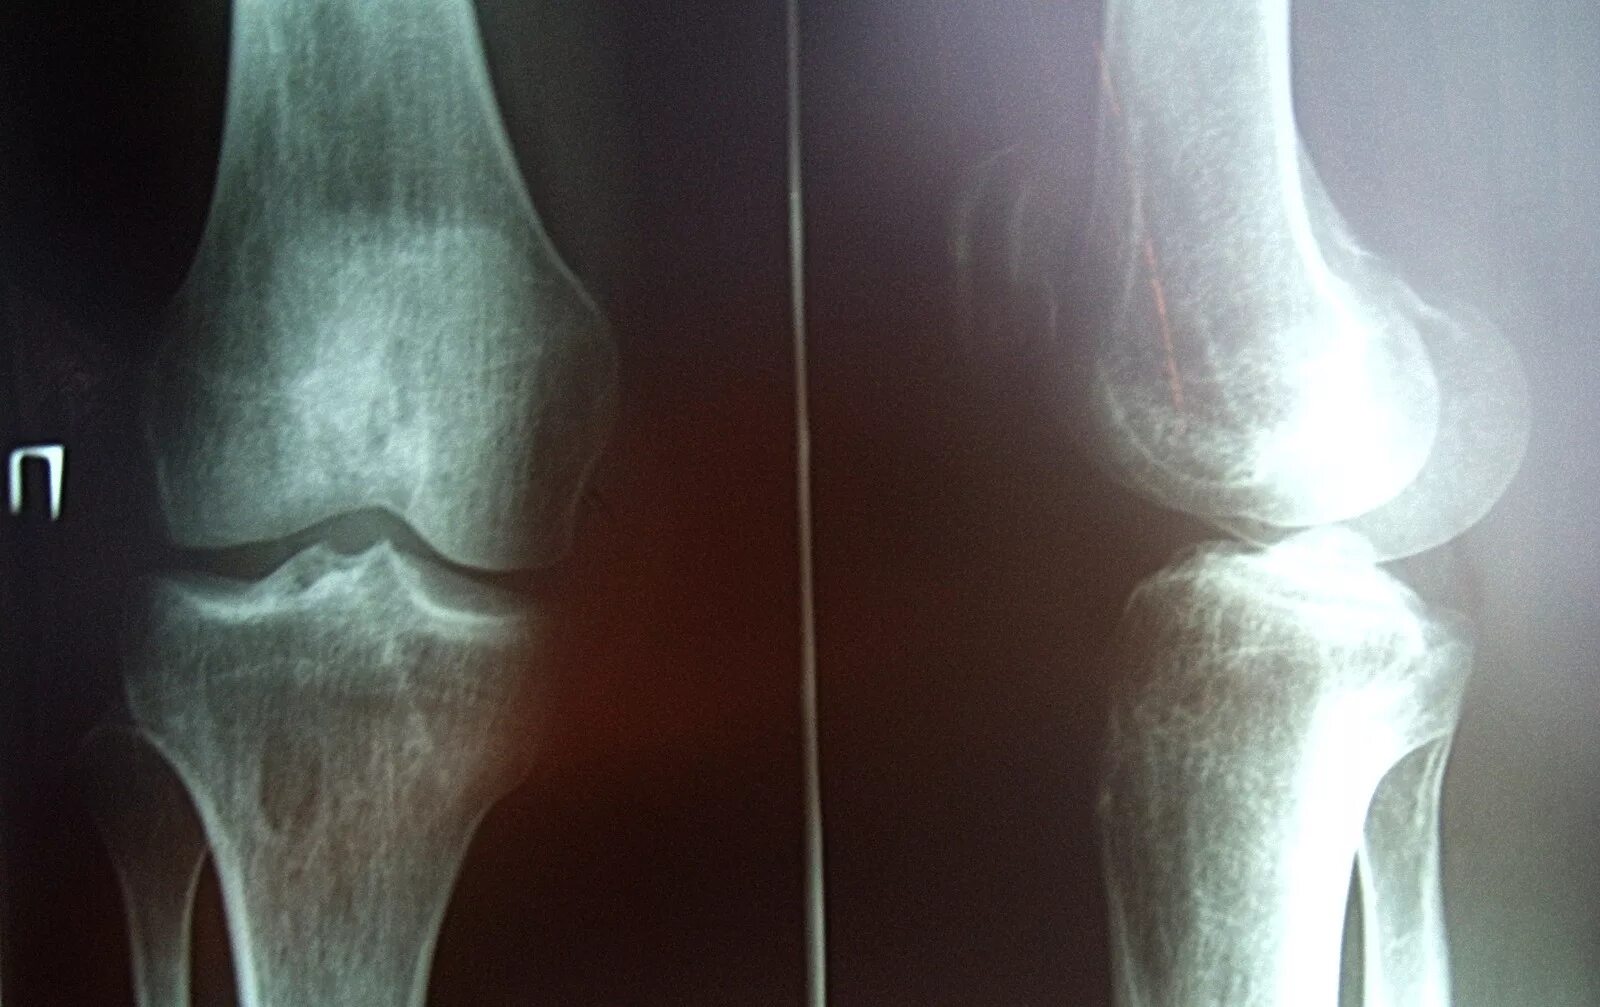

Перелом коленного сустава мкб